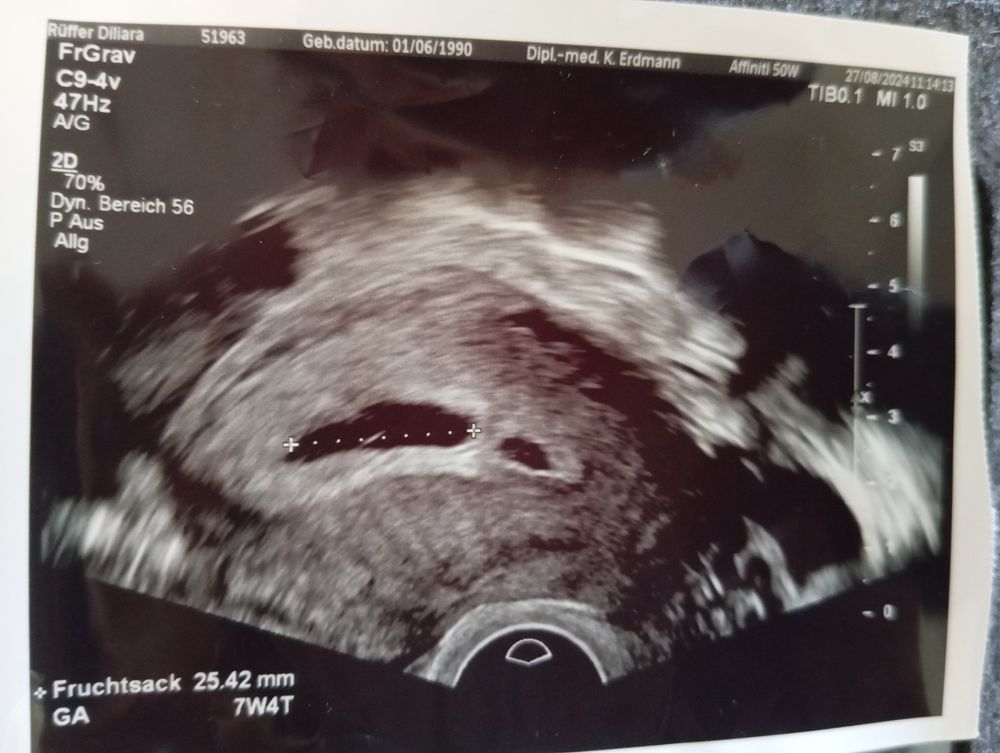

УЗИДевочки, у меня вопрос, по узи срок 7+4, пя 25, но похоже пустое. По месячеым 6+4. Я пошла к врачу, только из-за кровртечения , оказывается у меня скорее всего 2пч было и одно вышло. Второе пока в норме.Все признаки беременности на месте, тошнота, грудь стала немного больше, слабость.

Вот на фото ваш желточный мешочек

Karmilla, про жм врач ничего не сказала...немцы эм..немного другие, детального анализа не дают. А пя по узи 25мм. Я картинку прикрепила...там пусто, я ей так и сказала, но она отправила на неделю домой..

Вообще пишут, что если при ПЯ больше 25 мм нет эмбриона, то это анэмбриония(